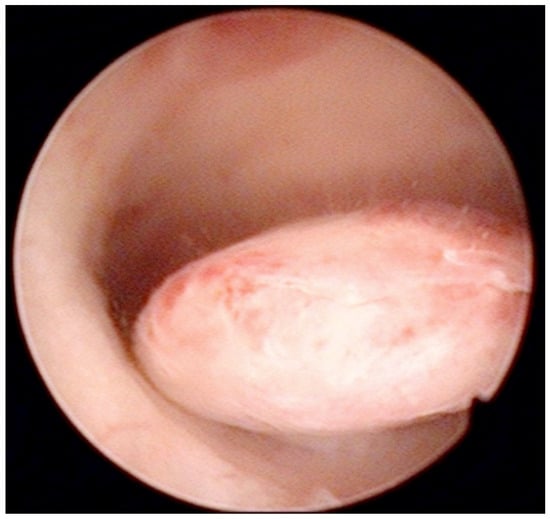

Similarly, Garuti et al. [42] used the terms “hysteroscopy” and “hysteroscopic view” interchangeably, reporting a low sensitivity (0.64 and 0.61) and specificity (0.92 and 0.95) for the diagnosis of endometrial hyperplasia. In the study of De Franciscis et al. [43], the concordance between the final histopathological result and the hysteroscopic impression was 86% for benign disease or normal endometrium, but only 58% for endometrial hyperplasia. In addition, the lowest agreement (52%) was noted for postmenopausal endometrial hyperplasia. When restricted to women with postmenopausal AUB, the sensitivity and specificity of in-office hysteroscopy for endometrial hyperplasia (with histopathology as reference) was 87% and 43%, respectively [43]. In contrast, Tinelli et al. [44] not only confirmed the diagnostic superiority of hysteroscopy with an eye-directed biopsy for detecting endometrial pathologies compared to TVS (and thus recommended hysteroscopy for all postmenopausal women with AUB and endometrial thickness > 4 mm) but also demonstrated the unique efficiency of hysteroscopy for diagnosing focal abnormalities (including EC) in the atrophic endometrium that would otherwise likely be missed by TVS. The authors advocate hysteroscopic evaluation even in patients with AUB with endometrium on TVS of <4 mm, aiming to decrease the chance of failing to diagnose carcinomas that develop focally in the atrophic endometrium (Figure 3) [44].

Figure 3.

Ultrasonographic appearance of uterine lesion suspected for early-stage endometrial cancer (A). The diagnostic hysteroscopic allows for visualizing the suspected uterine area (B) and for obtaining the histologic biopsy (C,D). Intraoperative photographs by F.B. and S.F.